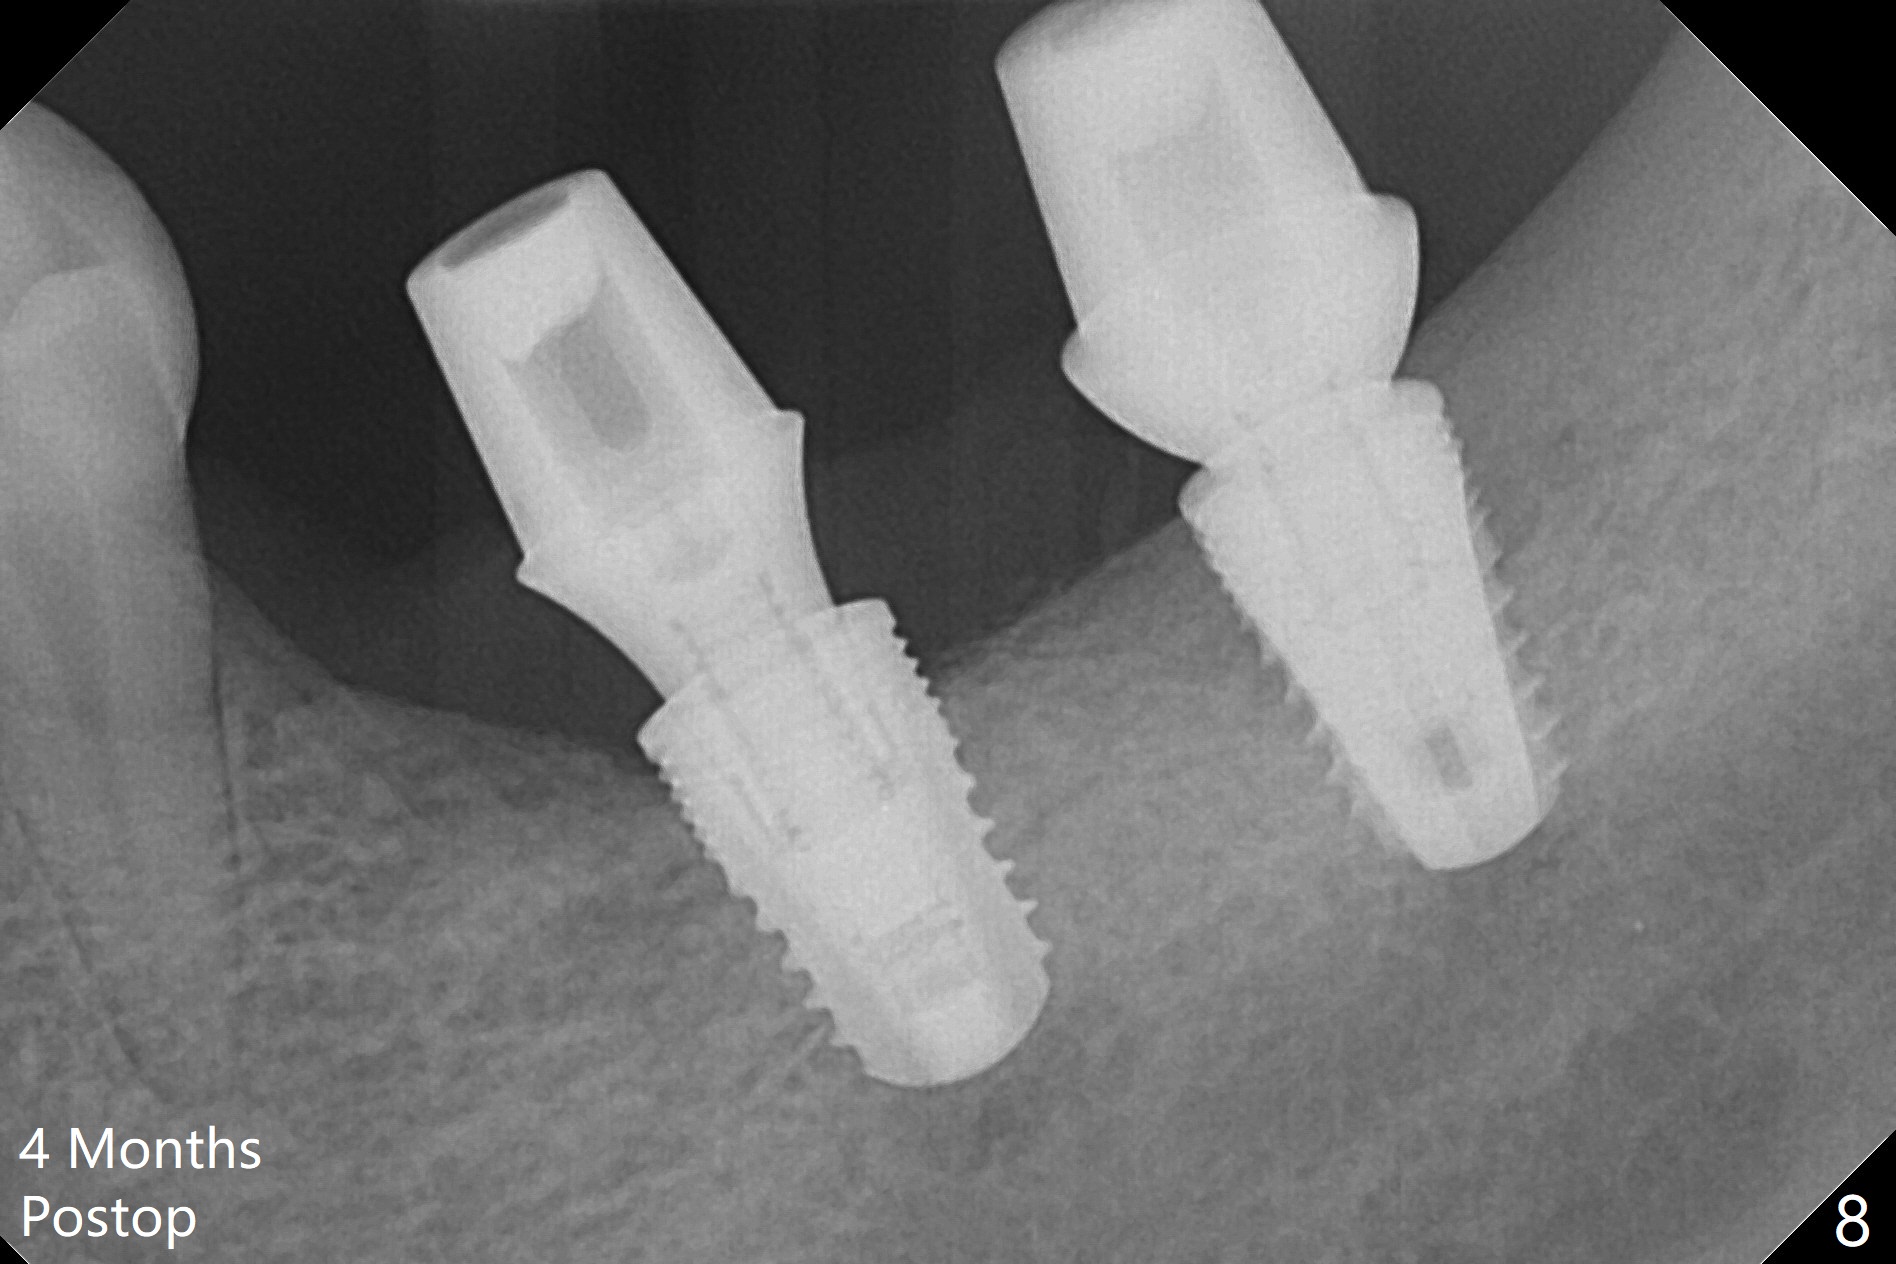

Preop photo shows severe mesial tilt of the tooth #18 (Fig.1). After extraction, the osteotomy is established in the apical end of the socket, where the buccolingual width is limited. It appears that an extra wide implant (5.9 mm) may perforate one of buccolingual plates. On the other hand, the buccal plate (Fig.2 double arrows) is intact and approximately 2 mm tall, whereas the lingual one is thin and lower. Initial osteotomy confirms that bone heights at #18 and 19 are 6 and 8 mm, respectively. Counting 2 mm of the buccal plate and bone graft lingually, a 8 mm long implant may be a practical option at the site of #18. After initial placement of two of 5x8 mm SM implants (Fig.3), the depth of the implant at #19 is adjusted twice (Fig.4,5). With placement of autogenous and allograft (Vanilla, Fig.5 *)) and abutments, a piece of cotton pellet is placed in each abutment well (access, Fig.6 *). Periodontal dressing is applied to the abutment wells for additional retention (Fig.7 *). Due to local poor oral hygiene, splinted provisional is fabricated 4 months postop (Fig.8) in preparation for limited orthodontic uprighting the tooth #20. The patient has pain with mastication at #18 eleven months post cementation (Fig.9). It appears that both of the implants should be removed with immediate replacement and bone graft. Prepare 4 PRF and sticky bone. The new implant will be 5.0 or 5.5x5 mm (Fig.10 green) with 2.3 mm platform (white). A block graft will be harvested from the ipsilateral ramus using 9/8 and 6/5 mm trephine burs for 2-3 mm in depth (Fig.11 blue). The ring graft will be seated around the platform over the implant (Fig.12).